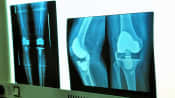

What Is Knee Osteoarthritis?

Knee osteoarthritis can affect daily activities. Changes in the knee’s cartilage, bone, and other soft tissues can lead to pain and stiffness.

Knee Osteoarthritis Video

This video gives an overview of the symptoms that appear with knee osteoarthritis joint deterioration.